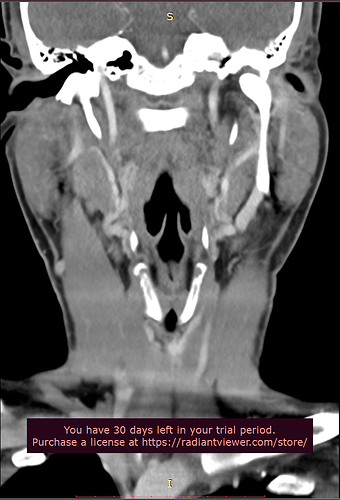

Please do a CT VENOGRAM of the brain and cervical spine with contrast. Please do a 3D reconstruction to show styloids. Please also measure the styloids.

Patient with symptoms of intracranial hypertension (pseudotumor cerebri) compatible with compression of the internal jugular vein at the transverse process of atlas (C1) or styloid process. Please do the scan in neutral.

Please make sure the CT Scan is capture while the contrast is in the internal jugular vein. This patient is suspected of having significant compression of the internal jugular vein(s) between the styloid bone and/or atlas. This is not a CT angiogram order it is a venogram. Surgical decisions will be made based on this scan.